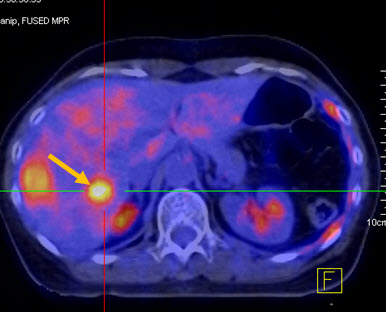

3. Chẩn đoán phát hiện di căn xa, đánh giá giai đoạn bệnh

Hình 3 là hình chụp PET/CT của bệnh nhân Bùi T. D., nữ, 28 tuổi, chẩn đoán ung thư vú phải. Trên hình toàn thân cho thấy chỉ có tổn thương u vú phải tăng hấp thu FDG mạnh, chưa có tổn thương di căn xa.

Hình 3: Hình khối u ác tính vú phải tăng hấp thu FDG mạnh (mũi tên). (Nguồn: Mai Trọng Khoa – Trung tâm Y học hạt nhân và ung bướu – BV Bạch Mai)

Hình 4 (a, b) cho thấy giá trị của PET/CT trong đánh giá giai đoạn của ung thư vú. Bệnh nhân Nguyễn Th. T. Tr., nữ, 63 tuổi, chẩn đoán là ung thư vú. Kết quả PET/CT toàn thân cho thấy nhiều tổn thương di căn hạch cổ, hạch trung thất, di căn 2 phổi, gan, xương tăng hấp thu FDG.

Hình 4a. Hình PET toàn thân thấy nhiều tổn thương hạch cổ, hạch trung thất (mũi tên vàng), phổi (mũi tên đỏ), gan (mũi tên tím) và xương (mũi tên xanh) tăng hấp thu FDG.

Hình 4b. Hình PET/CT ở mặt phẳng cắt ngang thấy tổn thương di căn phổi (mũi tên đỏ) và di căn gan (mũi tên da cam).